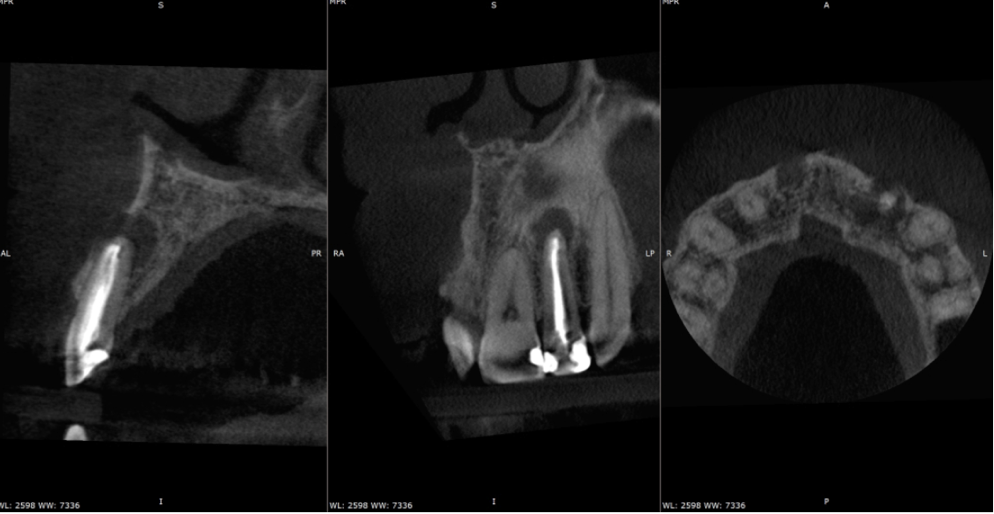

Re-treatments were completed for both teeth. However, due to the size of the apical lesions the patient was consented for the possibility of follow-up RES on either tooth. GP removal was completed using Dentsply’s ever dependable Reciproc Blue R25 and a combination of ultrasonics, Braided H files and the brilliant Gutta Percha Removal Instrument by Yoshi Terauchi available from Toothsaver. Enhanced irrigation protocols were used for both teeth utilising the excellent XP-endo Finisher. The UR1 was an open apex case. Having recently attended the IFEA World Endodontic Congress 2024, I was inspired by a re-treatment lecture I attended by Yoshi Terauchi and decided to implement one of his strategies (avoid use of gp in re-treamtents!) and use Well Root BC putty used in conjunction with Onefill BC sealer for the full obturation of the UR1. This had the added benefit of future proofing this tooth for RES surgery should this case fail to heal. Each tooth was completed over two visits (4 appointments in total for this case) using calcium hydroxide as an inter-visit dressing which resulted in full sinus resolution next to the UR1. Each root filling was sealed with RMGI and plugged with composite before being sent back to RD for internal whitening and veneers.

Post-op IOPA’s

Overall, a good result with both teeth and a nice lateral fill on the UL2. A 1-year CBCT review is planned to assess the healing of this case which the patient was fully on board with. I’ll add this in once I have it.